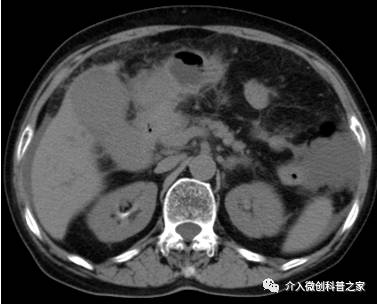

中晚期胰腺癌的供血动脉化疗药物灌注术

(高浓度药物靶向灌注杀死癌细胞)